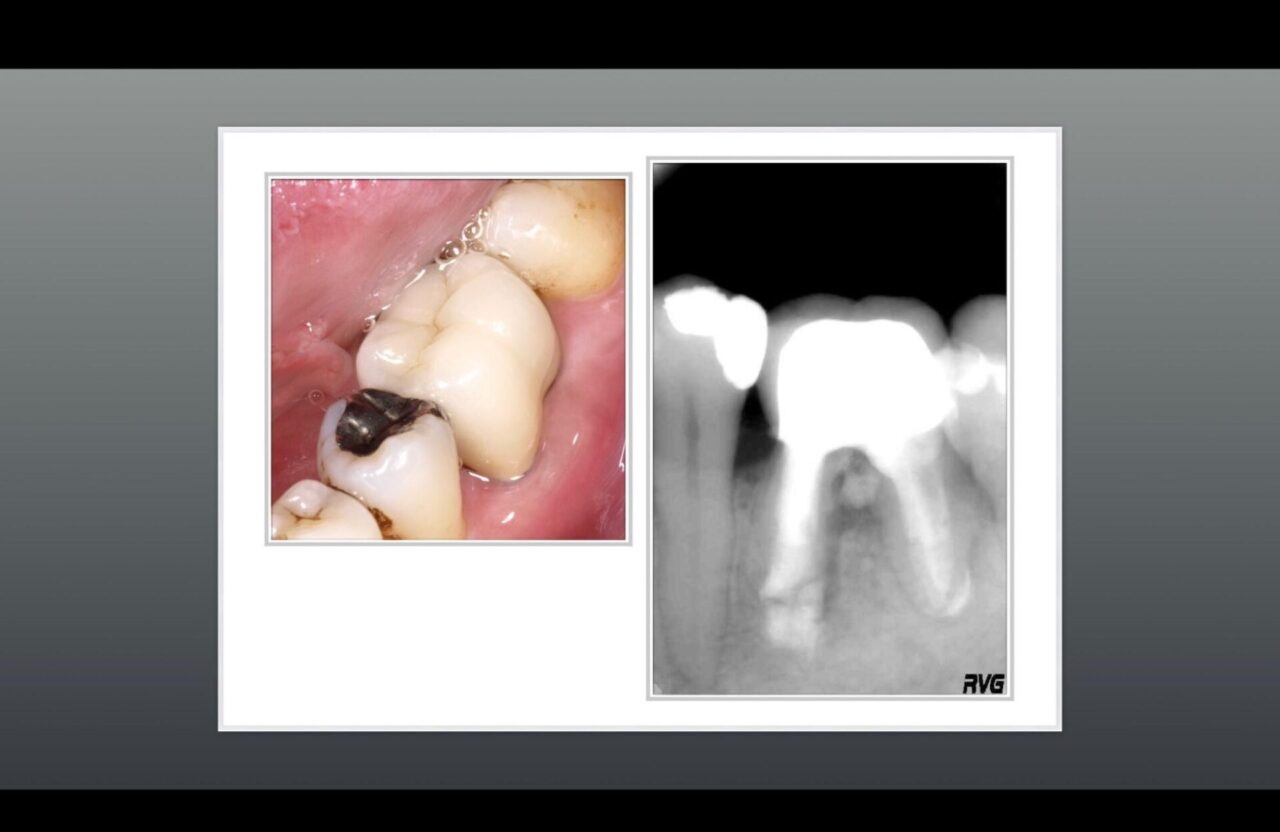

術前と術後のレントゲン①

術前と術後のレントゲン 大きな骨欠損が治り、骨の再生が確認できる。